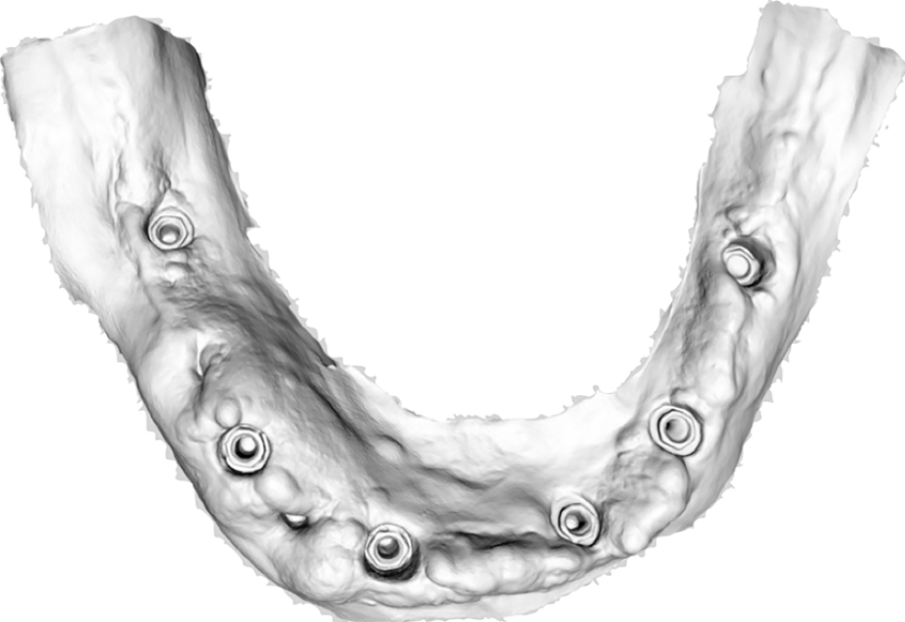

Dopo la rimozione dei denti residui e degli impianti, il paziente è stato immediatamente riabilitato con due protesi totali rimovibili diagnostiche in RP, che hanno migliorato i rapporti intermascellari, la VDO, OB, OJ, fonetica ed estetica. È stato eseguito un tracciato cefalometrico su una radiografia laterale del cranio per una valutazione funzionale iniziale del caso, seguita da una pianificazione protesica virtuale (Fig. 4), quindi radiologica (Fig. 5) e chirurgica. Le caratteristiche delle protesi studiate hanno determinato la pianificazione chirurgica (Smop, SwissMeda) (Fig. 6) e due guide chirurgiche sono state successivamente sinterizzate al laser (2Ingis) (Fig. 7). Gli impianti sono stati quindi posizionati come programmato (Figg. 8, 9), ad eccezione di quelli ai mascellari posteriori, dove è stato eseguito bilateralmente un grande rialzo del seno mascellare (Fig. 10).

Dopo due mesi è stata eseguita una scansione (Fig. 11) e i modelli in stampa 3D successivamente prodotti sono stati zoccolati per articolatore e ri-virtualizzati (Fig. 12) utilizzando un desktop scanner (inEos X5, Dentsply Sirona). I rapporti intermascellari e la posizione degli impianti sono stati accuratamente registrati, duplicando le protesi provvisorie in resina trasparente e fissando in bocca le posizioni dei transferts sui duplicati. La passività e precisione dei transferts in occlusione devono in questa fase essere controllate con estrema accuratezza. L’occlusione dei duplicati è usata quindi per il montaggio dei modelli zoccolati, che sono stati fissati su basi di montaggio con un arco facciale in un articolatore arcon completamente regolabile (Reference SL, Gamma Dental).